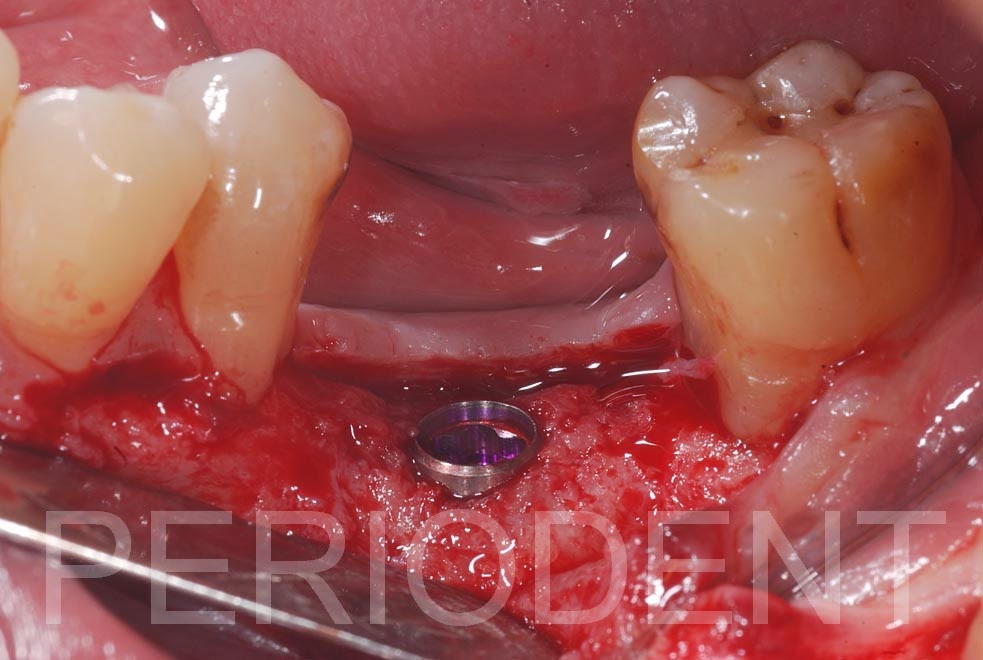

拔牙完七個月進行植牙,並再度補骨